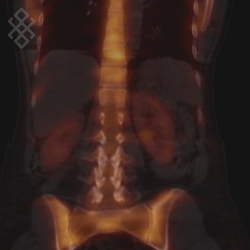

Scintigraphie Osseuse

La première partie de l'examen durera entre 15 et 30 minutes. Ensuite, il y aura une pause d'environ 3 heures. Enfin, la deuxième partie de l'examen durera 1 heure. L'acquisition des images peut commencer dès l'injection du traceur radioactif. Durant les deux parties de l'examen, des séries d'images pourront être réalisées (de profil, de face, du corps entier...). Pour une qualité optimale de l'examen, l'appareil sera positionné proche de vous pour ensuite se déplacer et tourner autour de la table d'examen.